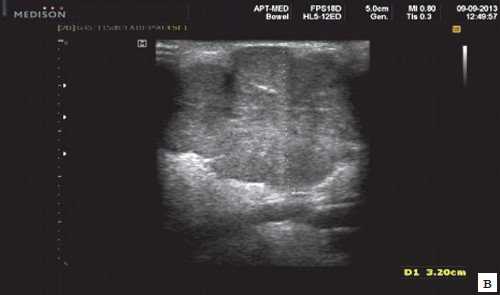

В отечественной и зарубежной литературе встречается много работ, посвященных сиалогии (от греч. Sialon - слюна и logos - учение) - науке о заболеваниях и повреждениях слюнных желез, методах их диагностики и лечения. По данным разных авторов, на долю заболеваний слюнных желез приходится до 24% всей стоматологической патологии. В настоящее время в клинической практике наиболее часто встречаются дистрофические, воспалительные заболевания слюнных желез (сиалоаденозы, сиалоадениты), а также опухоли и врожденные пороки развития слюнных желез. Кроме того, патологические изменения слюнных желез часто сопутствуют другим заболеваниям (сахарный диабет, бронхоэктатическая болезнь, саркоидоз, цирроз печени, гипертриглицеридемия, лимфогранулематоз и др.).

- ультразвуковой метод (является наиболее доступным, безопасным и информативным в процессе дифференциальной диагностики патологического состояния слюнных желез).

Опухоли слюнных желез

Опухоли слюнных желез подразделяются на две группы: эпителиальные и неэпителиальные. Эпителиальные опухоли преобладают у взрослых (95%). У детей в СЖ эпителиальные и неэпителиальные опухоли встречаются одинаково часто. Помимо истинных опухолей в СЖ развиваются процессы, напоминающие опухоли (опухолеподобные поражения).

Среди эпителиальных опухолей СЖ различают доброкачественные новообразования, а также злокачественные - карциномы.

К доброкачественным эпителиальным новообразованиям СЖ относят папилломы протоков, аденомы и доброкачественную сиалобластому. Аденомы СЖ делят на две группы: полиморфные (самая частая аденома СЖ) и мономорфные (все остальные) аденомы. В группу мономорфных аденом были искусственно включены опухоли разного строения, происхождения и прогноза.

Плеоморфная (полиморфная) аденома (смешанная опухоль СЖ) - аденома СЖ, построенная из двух типов клеток: эпителия протоков и миоэпителиоцитов. Макроморфологическая картина. Опухоль обычно представляет собой эластичный или плотный узел дольчатой серовато-белой ткани, как правило, инкапсулированный частично. Типичной для плеоморфной аденомы является так называемая хондроидная строма, напоминающая гиалиновый хрящ. Варианты эхографического изображения плеоморфных аденом представлены на рисунке 8.

Рис. 8. Плеоморфная аденома СЖ.